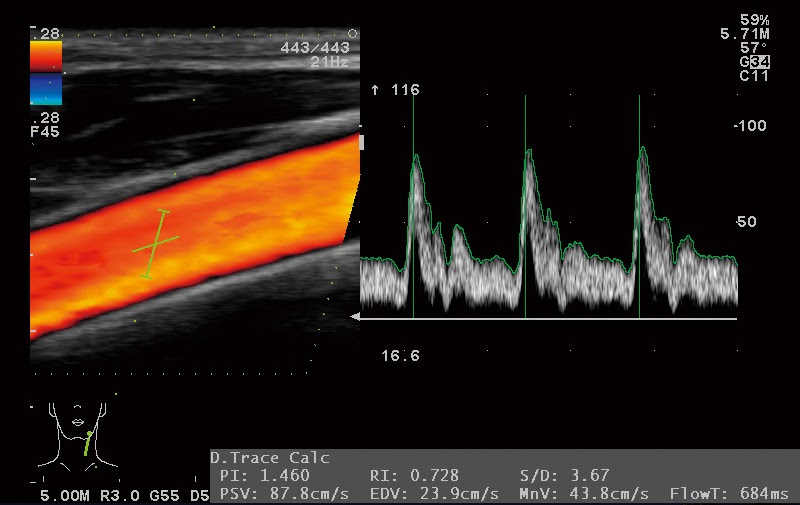

Автоматический расчет комплекса интима-медиа и оценка сокращений миокарда

EUP-L73S – Низкочастотный линейный датчик для исследования глубоких структур. Обладая низкой частотой, данный зонд обеспечивает высокую глубину проникновения. Такая особенность позволяет эффективно использовать датчик, к примеру, при исследовании сосудов нижних конечностей.

Датчик также подходит для акушерских исследований, благодаря широкому полю обзора в трапецеидальном режиме.